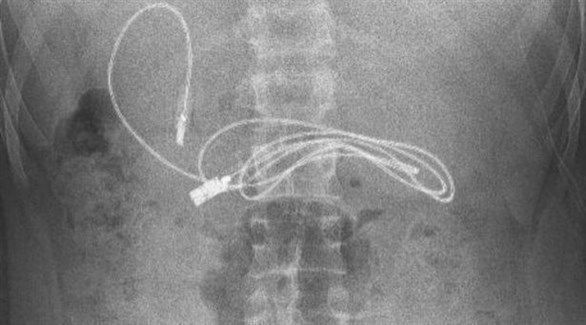

صدم مراهق الأطباء، بعد نقله إلى أحد مستشفيات تركيا وهو يعاني من غثيان شديد وآلام مبرحة في معدته، إذ أظهرت الأشعة المقطعية، ابتلاعه سلك شاحن طوله 90 صنتيمتراً.

وقال الطبيب الذي أشرف على الجراحة، إن العملية كانت معقدة لأن أحد طرفي السلك مَر إلى الأمعاء الدقيقة. ولحسن الحظ، تعافى المراهق، 15 عاماً، سريعاً بعد العملية وعاد إلى منزله في ديار بكر بصحة جيدة.